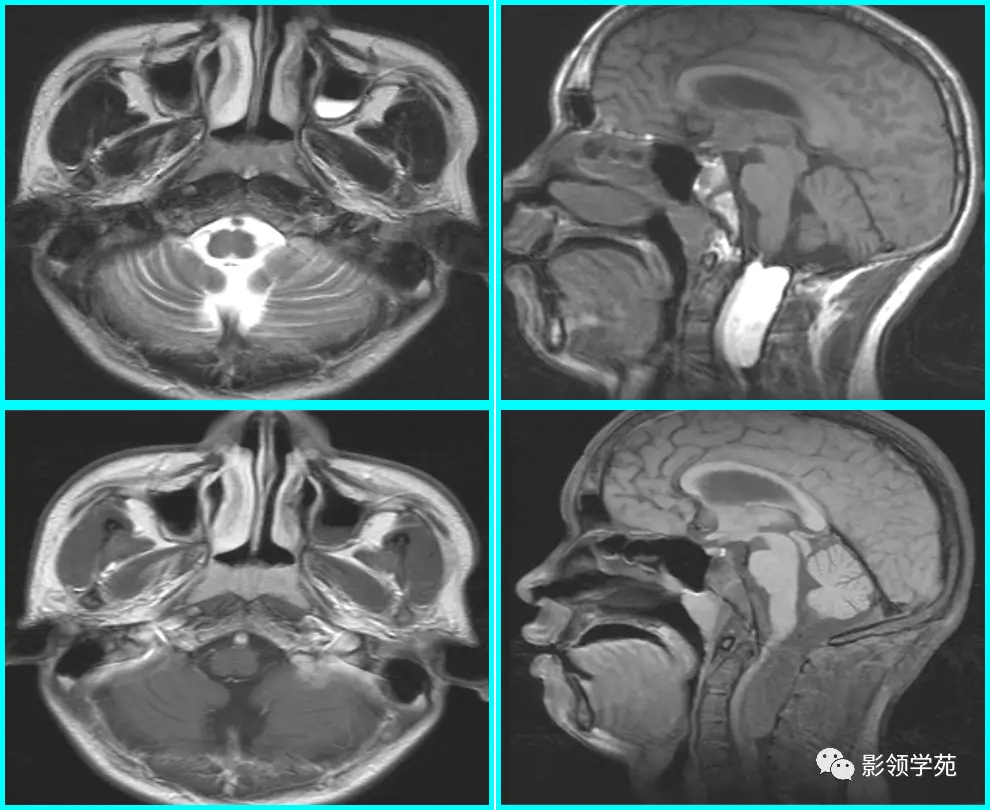

儿童腺样体肥大影像表现及诊断标准